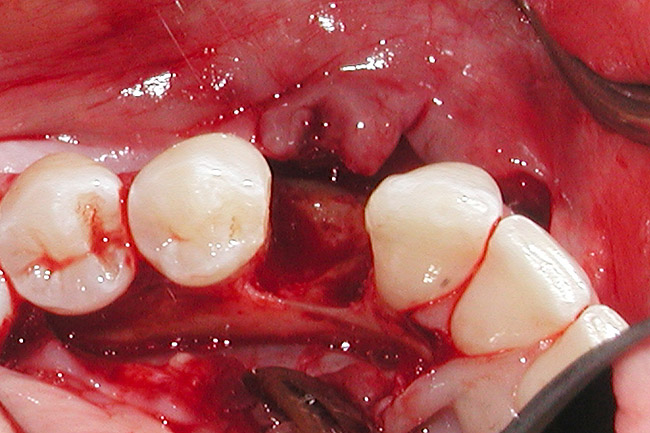

Figure 6  Mucogingival and residual defect after removal of implant in site No. 22.

Figure 6

The patient had no medical concerns and had a history of an implant placement in December 2002 when she was 25 years old. In February 2005, she presented with a mobile implant and an associated advanced peri-implantitis. Radiographic review at the initial examination demonstrated significant destruction of the dentoalveolar ridge around the implant as well as around the adjacent natural dentition. Emergency-based treatment involved surgical implant removal only and debridement of the infection (Figure 4 and Figure 5). Following uneventful healing, an advanced ridge defect was apparent at the edentulous site and moderate and advanced attachment loss noted at No. 22D and No. 21M, respectively (Figure 6 and Figure 7). This case demonstrates bone loss of two separate origins: lack of bone because of tooth agenesis and destruction of bone from inflammatory peri-implantitis.

This treatment plan was elected with the premise to reevaluate treatment options during orthodontic tooth movement. Soft-tissue augmentation was initiated to correct the mucogingival defect in the area of teeth Nos. 21 and 22. A free gingival graft was performed to achieve an adequate band of attached and keratinized gingiva to resist potential stripping on the root surfaces of teeth Nos. 22 and 21 during orthodontic movement (Figure 8). Orthodontic movement then was initiated to site-develop position No. 23 for an implant (Figure 9 through Figure 11). Orthodontics also was used to idealize the patient’s occlusion and develop canine guidance to minimize occlusal load and maximize the redistribution of forces36-40 for protecting the future implant from deleterious forces. The space was opened around the peg lateral tooth No. 7, and the gingival levels were aligned for maxillary incisors. Bonding was performed to restore the length of teeth Nos. 8 through 10 and to bond the peg lateral to a normal tooth form, which allows the orthodontist to idealize the posterior occlusal scene and maintain canine guidance (Figure 12 through Figure 13).